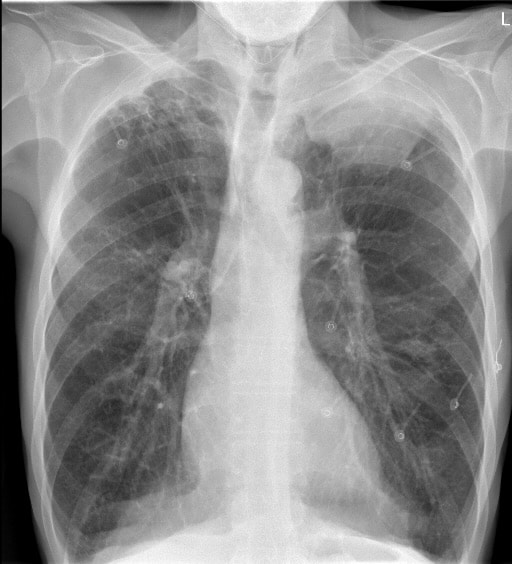

Pancoast Tumour

Pancoast Tumour is a primary bronchogenic carcinoma which arises in the apex of the lung at the superior pulmonary sulcus.

Fig. 3 (case 7).—Roentgenogram of the chest, showing the circumscribed apical shadow. Note the upper arrows pointing to the second rib and to the head and neck of the first rib, both of which are intact. Pancoast 1932